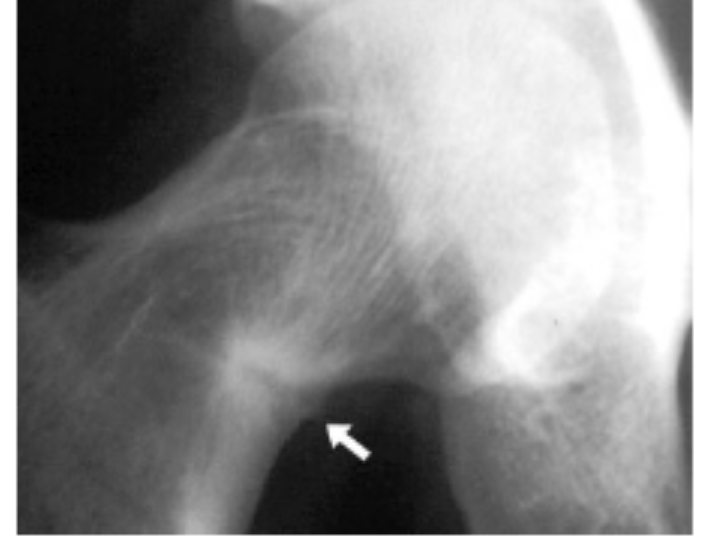

describe the radiograph in osteomalacia